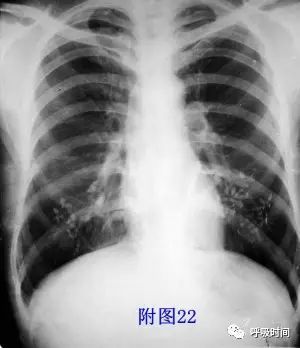

图片

图 22 男 45 岁,发烧胸痛 3 天,T 39℃

原描述:片示下肺野钙化;考虑胸膜钙化。

仔细观察,实际为衣物上的漆字:第三---口普查